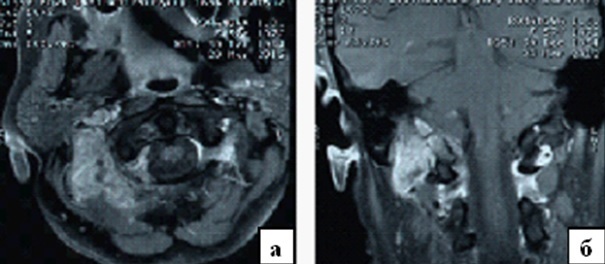

Кранио вертебральный переход

Кранио вертебральный переход 115 фото